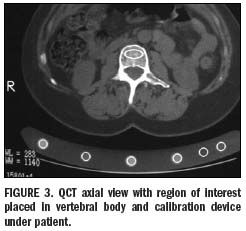

Measurements of trabecular bone in consecutive vertebrae of the spine (usually two to four vertebrae between T12 and L4) can be made from axial CT images using a bone mineral reference standard to calibrate each scan (Figure 3). Results are usually given as T-scores and Z-scores, as for all bone densitometry techniques.